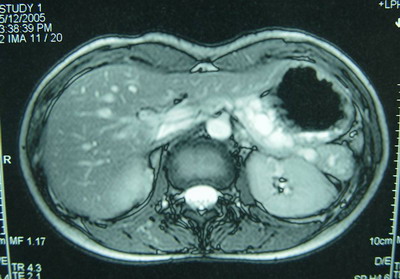

胰腺MRI